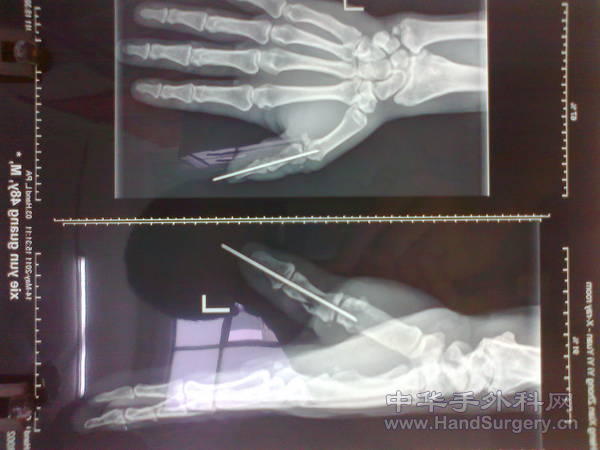

照片0237.jpg 照片0236.jpg 照片0235.jpg 照片0232.jpg 照片0231.jpg 照片0230.jpg 这是个“三角带”绞断的拇指,尺掌侧固有动静脉、神经仍包含在残存相连的组织内,因此只需要骨折内固定即可,皮肤约有1/4存留,肌腱:拇长伸、拇长展、拇短展、拇长屈离断,其中拇长展、拇长屈是两个平面离断,很难拉,断端呈絮状,不得已还借了点侧副韧带来桥接(病人没钱,四千块钱全家想了两个小时,甚至说反正是副手,截掉算了),没做肌腱移植。

看照片好像有血运!骨折居然穿糖葫芦了!

这个骨折并不像X片上看着这么好,其实近节已经碎到了基底部,只有大约1公分是完整的,所以只能打穿掌指关节固定于功能位